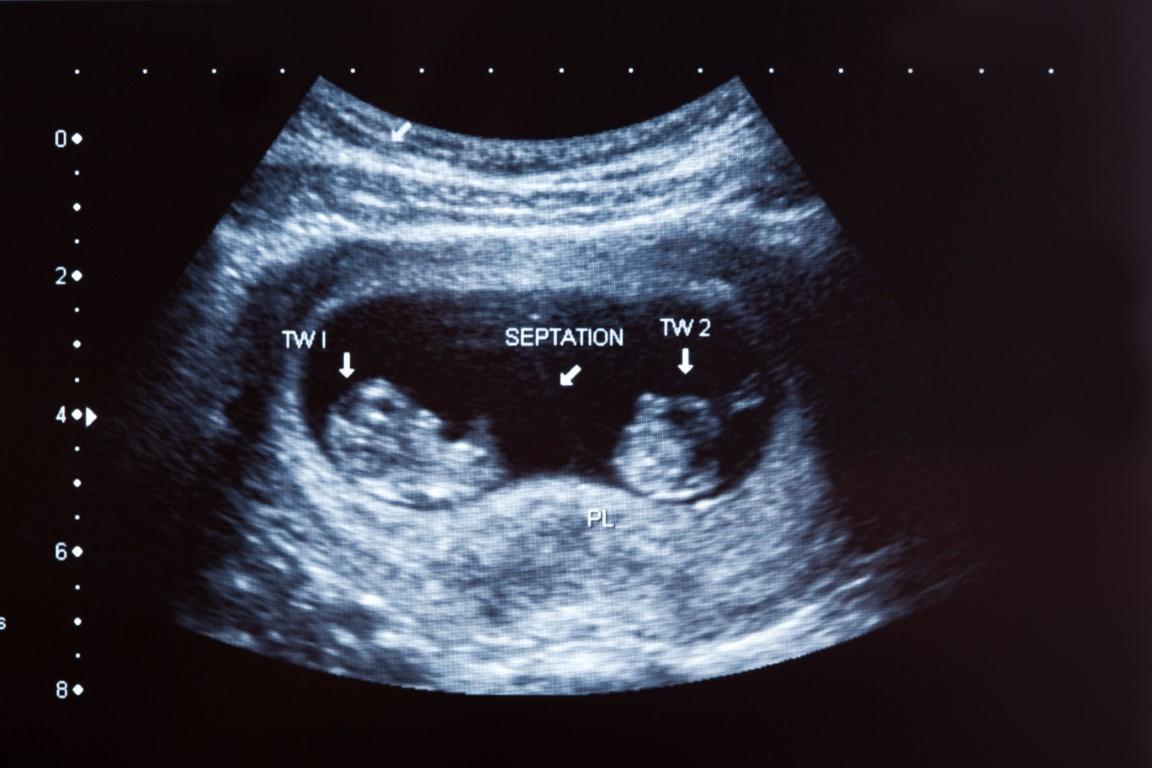

Riskli gebelikler ayrıntılı ultra. Perinatoloji muayenesinde anne adayının genel sağlık durumu önceki hastalıkları geçirilmiş gebelikler ve bunların nasıl sonuçlandıkları ayrıntılı olarak sorgulanır.